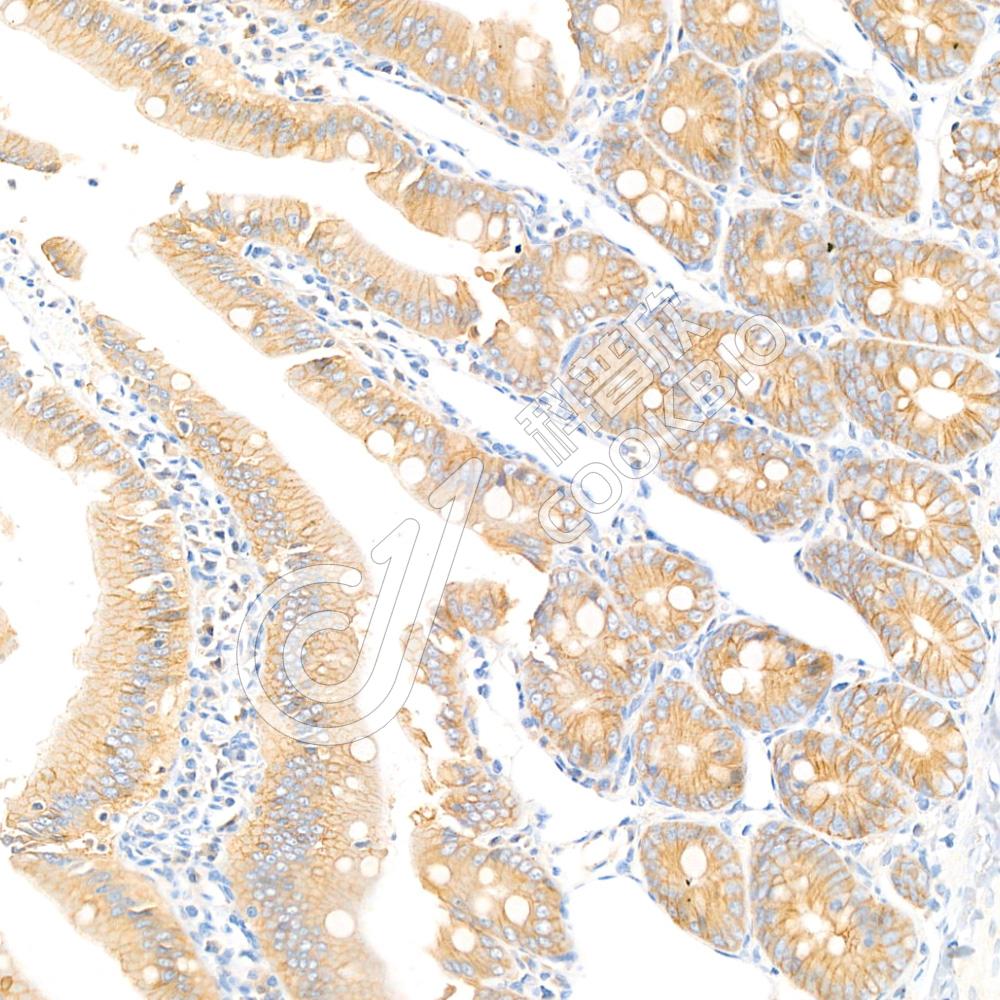

IHC检测Occludin蛋白(货号 K1334203).

样品: 大鼠结肠, 4%多聚甲醛 (货号KSG1101) 固定12-24小时.

抗原修复: 柠檬酸抗原修复液(干粉, pH 6.0) (KSG1201), 98℃, 20分钟.

—抗: 1: 1000稀释, 4℃ 孵育过夜.

二抗: S-vision免疫组化多聚二抗(山羊抗兔),即用型 (货号KB3906), 室温孵育20分钟.